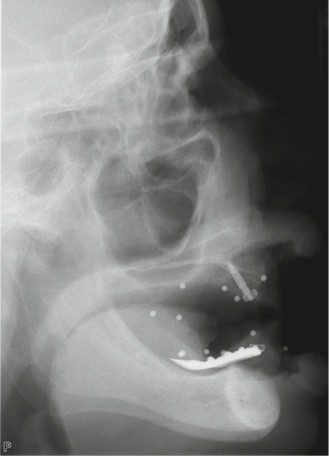

- appui muqueux : sa précision est inférieure. Réservé aux cas d’édentement total, il est conçu à partir d’un alignement avec une prothèse amovible complète comportant des marqueurs radio-opaques (fig. 5 à 8). Le risque d’imprécision est majoré par la dépressibilité de la muqueuse, la tuméfaction des tissus mous due à l’anesthésie, ou le positionnement initial en s’aidant de l’occlusion ;